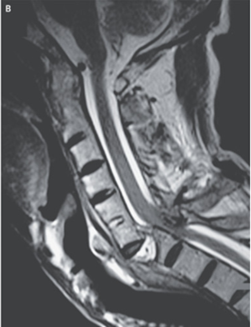

頸椎MRIも施行。脊髄圧迫が確認された。

身体検査では、C6以下仙髄を含む運動機能が残存せず、知覚は残存していた。下部頚髄の急性圧迫所見と判断された。